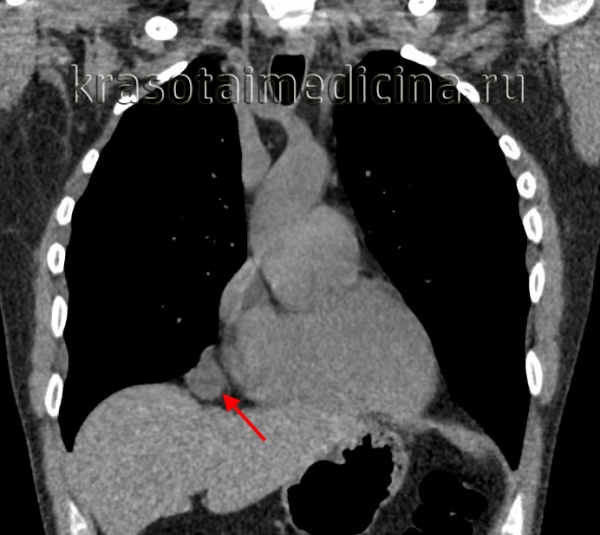

Пример дермоидной кисты. Тератомы средостения

Тератомы средостения обычно располагаются в переднем средостении, рядом с крупными сосудами и перикардом. Долгое время никак не проявляются. Обычно начинают расти в подростковом возрасте или в период гестации. Могут увеличиваться до 20-25 см. Сдавливают легкие, сердце, плевру и кровеносные сосуды. Сдавление внутренних органов сопровождается учащением сердцебиения, болями в сердце, одышкой и кашлем. При прорыве тератомы средостения в бронх или плевральную полость возникает синюшность кожи, удушье, повышение температуры тела, асимметрия грудной клетки, икота, иррадиирующие боли в области надплечья на стороне поражения. Возможно легочное кровотечение и развитие аспирационной пневмонии.

Кистозные тератомы содержат в своей структуре элементы эктодермы и возникают в процессе нарушения эмбриогенеза. В медицине встречаются дермоидные кисты яичников, брюшной стенки, кожи, забрюшинной клетчатки, печени, почек и др. органов и тканей. Дермоидные кисты обычно расположены в передневерхнем отделе средостения. Величина дермоидных кист средостения может достигать 15-25 см. Форма кистозных тератом обычно неправильная овальная; консистенция эластическая или мягкая. Стенки кисты могут содержать хрящевые и известковые включения. Внутри кисты заключена густая кашицеобразная жирная масса с множеством различных включений (волос, чешуек эпидермиса, кристаллов холестерина, аморфных жиров, зубов).

Более чем в половине случаев дермоидная киста средостения сопровождается различными сердечно-сосудистыми нарушениями: приступами стенокардии, болью в области сердца, тахикардией. У 30% больных признаком дермоидной кисты средостения служит появление продуктивного кашля с выделением кашицеобразной массы, содержащей примесь волос и жира, что наблюдается при прорыве кисты в бронх. У части пациентов отмечается выпячивание грудной стенки в проекции расположения опухоли.